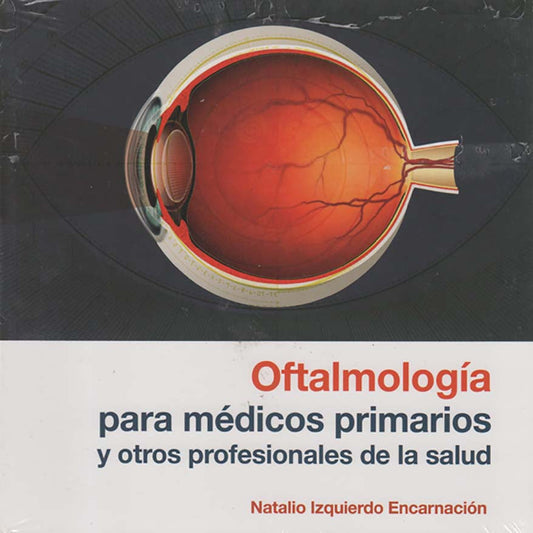

Oftalmología para médicos primarios y otros profesionales de la salud

Proveedor:Editorial UPRPrecio habitual $18.33 USDPrecio habitual -